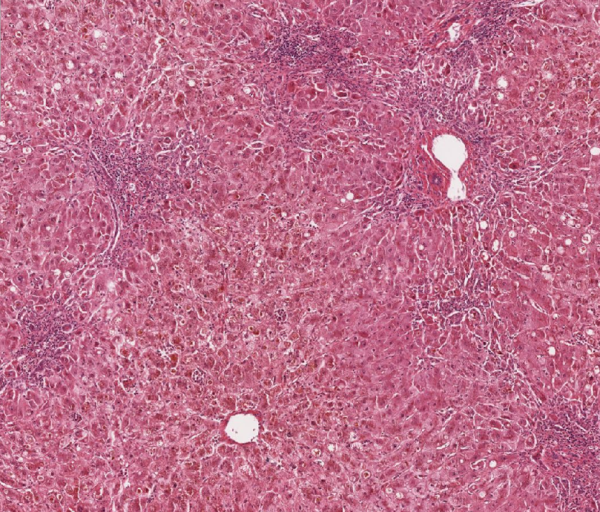

• Lebergewebe mit nodulärem Parenchymumbau

• Ausbildung bindegewebiger porto-portaler Septen bei teilweise noch erhaltene Zentralvenen (inkomplette Zirrhose)

• duktuläre Reaktion (reaktiv)

Abb. 673: Lebergewebe mit knotigem Umbau